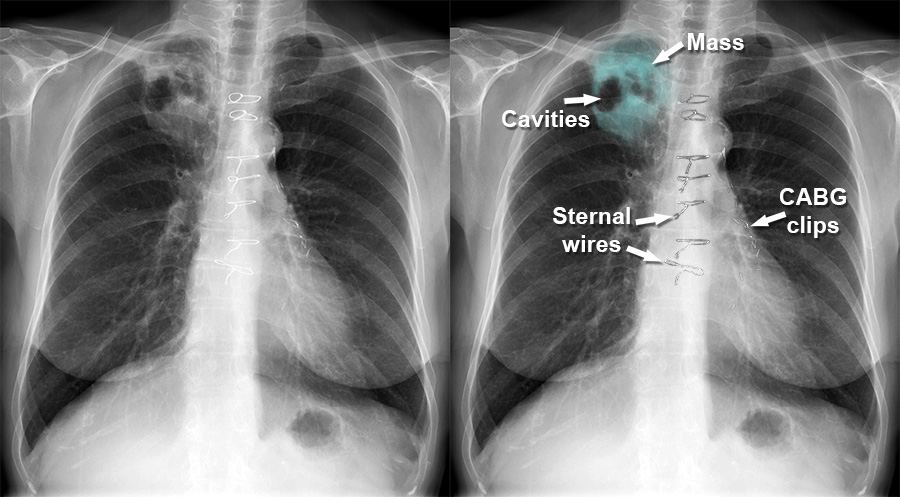

Lung Cancer Screening X Ray

Experience the clarity of Lung Cancer Screening X Ray with our curated collection of comprehensive galleries of images. featuring understated examples of photography, images, and pictures. designed to emphasize clarity and focus. Discover high-resolution Lung Cancer Screening X Ray images optimized for various applications. Suitable for various applications including web design, social media, personal projects, and digital content creation All Lung Cancer Screening X Ray images are available in high resolution with professional-grade quality, optimized for both digital and print applications, and include comprehensive metadata for easy organization and usage. Our Lung Cancer Screening X Ray gallery offers diverse visual resources to bring your ideas to life. Comprehensive tagging systems facilitate quick discovery of relevant Lung Cancer Screening X Ray content. Multiple resolution options ensure optimal performance across different platforms and applications. Time-saving browsing features help users locate ideal Lung Cancer Screening X Ray images quickly. The Lung Cancer Screening X Ray archive serves professionals, educators, and creatives across diverse industries. Instant download capabilities enable immediate access to chosen Lung Cancer Screening X Ray images. Whether for commercial projects or personal use, our Lung Cancer Screening X Ray collection delivers consistent excellence. Professional licensing options accommodate both commercial and educational usage requirements.